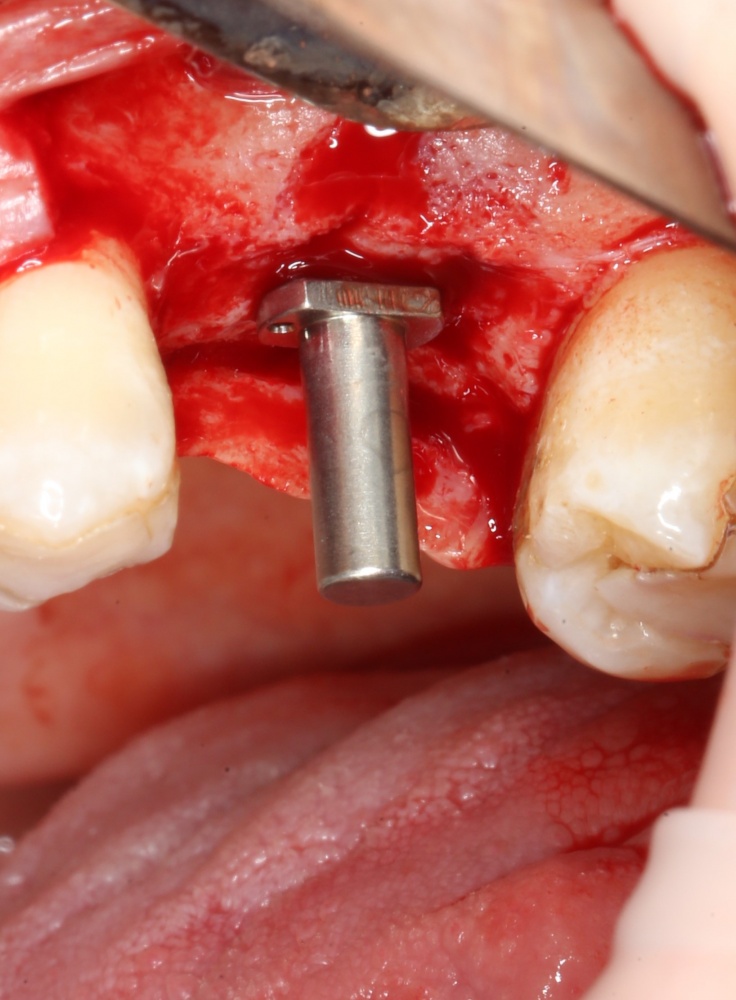

После этого можно еще раз (последний, кстати), проверить направление и ангуляцию оси будущего имплантата. Всё тем же вышеозначенным пином: